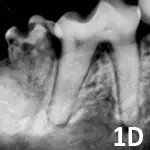

Stage 4: Extensive hard tissue loss. Most of the tooth loses integrity. In stage 4A (See Figure 1D), the crown and root are equally affected; in stage 4B (See Figure 1E), the crown is more severely affected than the root; in stage 4C (See Figure 1F), the root is more severely affected than the crown.

A dental radiograph shows the roots of a canine tooth, highlighting the surrounding bone structure and any potential abnormalities. The image provides a clear view of the tooth's anatomy, essential for diagnosing dental issues in veterinary patients.

Figure 1D

Mandibular second molar affected by stage 4A tooth resorption.